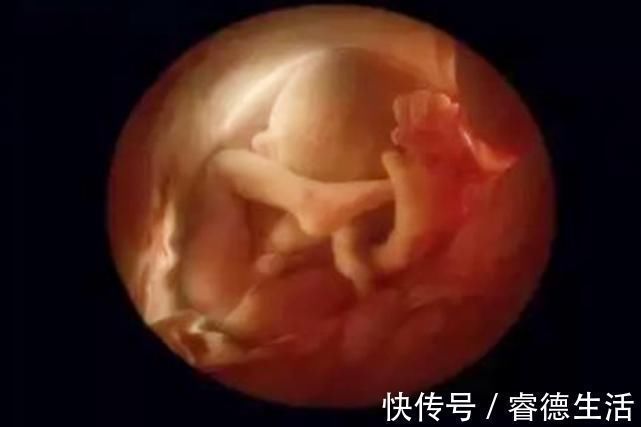

新生儿身高越接近这个数值,说明大脑发育得越好研究数据表明,当孩子的身高接近50cm左右的时候,就是他们“聪明”的标志。

那些在妈妈子宫内发育得很好的孩子,在出生后,身高都会在50cm左右,这说明孩子在生长期营养成分充足,孩子各方面的身体机能相对较。这样的孩子在以后的生长过程中,也不太容易生病,大脑的发育也会比较完善,要比同龄孩子更聪明一些。

而像那些在宫内发育不全的早产儿,往往出生后的身高就达不到这个数值,而且体重也比较轻,根本不达标。出生后也会更加容易生病和缺乏营养,智力自然也会受到相应的影响。

事实上,大部分宝宝在出生时,身高都会在50cm左右,虽然每个宝宝发育有差距,但在身高上,除去那些早产儿,几乎其他的新生宝宝身长都是50cm左右。